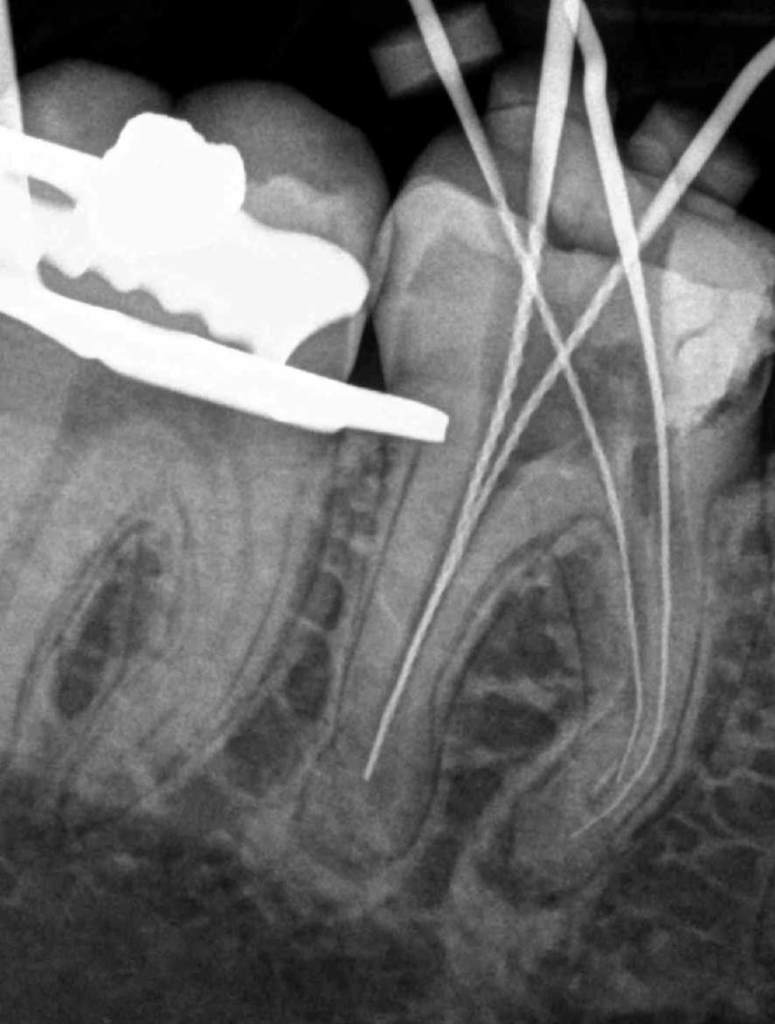

Reco preendo + 4 conductos molar superior